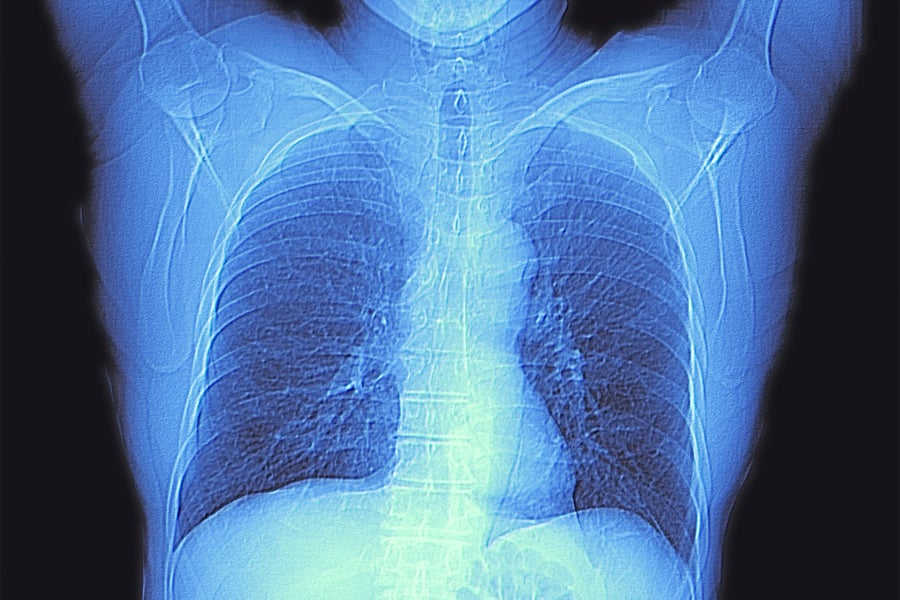

In addition to CT scans, pulmonary function tests are often used to diagnose lung disease. Alfred Pasieka/Science Photo Library/Getty Images